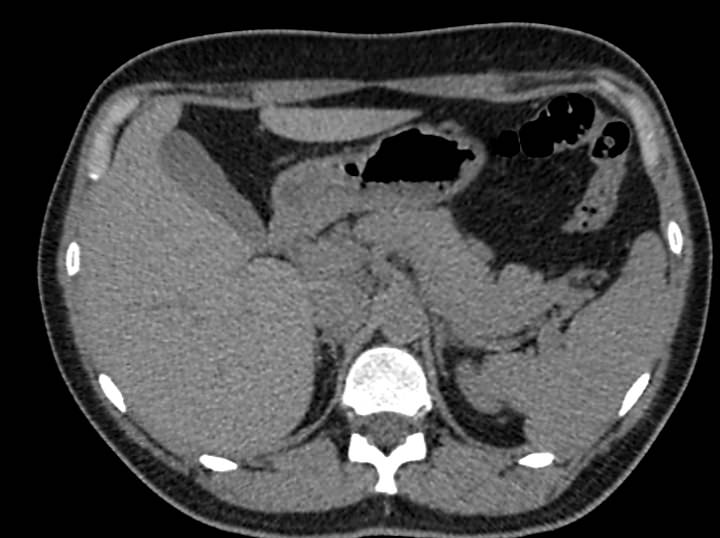

Мультиспиральная компьютерная томография желчного пузыря применяется для оценки состояния стенок желчного пузыря, изучения содержимого его полости, выявления воспалительных изменений, конкрементов и опухолевых новообразований.

В клинике «Доступная медицина» исследование проводится на новейшем 128-срезовом томографе TOSHIBA AQUILION CXL, который позволяет проводить исследование за короткий промежуток времени при сниженной лучевой нагрузке. Посредством инновационных компьютерных программ томограф преобразует полученные данные в 3D-изображения желчного пузыря и желчевыводящих протоков. Это помогает диагностировать заболевания гепатобилиарной системы особенно при нетипичной клинической картине, когда при помощи других методов обследования (УЗИ, МРТ) не удается выявить причину нарушения оттока желчи из желчного пузыря.

МСКТ желчного пузыря в большинстве случаев проводится с применением контрастирования. Пациенту внутривенно вводится рентгеноконтрастное вещество на основе йода. Препарат с током крови попадает в исследуемую область и усиливает контрастность патологических участков, что делает их видимыми на фоне здоровых тканей. При подозрениях на онкологический процесс метод компьютерной томографии с контрастированием помогает обнаружить патологию на раннем этапе развития и провести своевременное лечение.